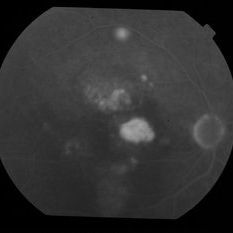

Central Serous Chorioretinopathy

FA&ICG late phase of a young woman with CSCR

Photographer: Filip Kecer, Oftalmocentrum Betliarska, Bratislava, Slovakia

Imaging device: Spectralis, Heidelberg Engineering

Condition/keywords: central serous chorioretinopathy (CSCR), Central Serous Chorioretinopathy (CSR), FA late phase, indocyanine green (ICG) angiography